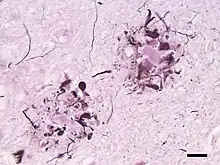

Amyloid plaques (also known as neuritic plaques, amyloid beta plaques or senile plaques) are extracellular deposits of the amyloid beta (Aβ) protein mainly in the grey matter of the brain.[1][2][3][4] Degenerative neuronal elements and an abundance of microglia and astrocytes can be associated with amyloid plaques. Some plaques occur in the brain as a result of aging, but large numbers of plaques and neurofibrillary tangles are characteristic features of Alzheimer's disease.[5] Abnormal neurites in amyloid plaques are tortuous, often swollen axons and dendrites. The neurites contain a variety of organelles and cellular debris, and many of them include characteristic paired helical filaments, the ultrastructural component of neurofibrillary tangles.[3] The plaques are highly variable in shape and size; in tissue sections immunostained for Aβ, they comprise a log-normal size distribution curve with an average plaque area of 400-450 square micrometers (µm²). The smallest plaques (less than 200 µm²), which often consist of diffuse deposits of Aβ,[4] are particularly numerous.[6] The apparent size of plaques is influenced by the type of stain used to detect them, and by the plane through which they are sectioned for analysis under the microscope.[4] Plaques form when Aβ misfolds and aggregates into oligomers and longer polymers, the latter of which are characteristic of amyloid.[7] Misfolded and aggregated Aβ is thought to be neurotoxic, especially in its oligomeric state.[8]

Amyloid plaques are visible with the light microscope using a variety of staining techniques, including silver stains, Congo red, Thioflavin, cresyl violet, PAS-reaction, and luminescent conjugated oligothiophenes (LCOs).[32][4][33] These methods often stain different components of the plaques, and they vary in their sensitivity[4][34] Plaques may also be visualized immunohistochemically with antibodies directed against Aβ or other components of the lesions. Immunohistochemical stains are especially useful because they are both sensitive and specific for antigens that are associated with plaques.

The Aβ deposits that comprise amyloid plaques are variable in size and appearance.[3][4] Under the light microscope, they range from small, wispy accumulations that are a few microns in diameter to much larger dense or diffuse masses. So-called 'classical plaques' consist of a compact Aβ-amyloid core that is surrounded by a corona of somewhat less densely packed Aβ.[4] Classical plaques also include abnormal, swollen neuronal processes (neurites) deriving from many different types of neurons, along with activated astrocytes and microglia.[3][4] Abnormal neurites and activated glial cells are not typical of most diffuse plaques, and it has been suggested that diffuse deposits are an early stage in the development of plaques.[35]